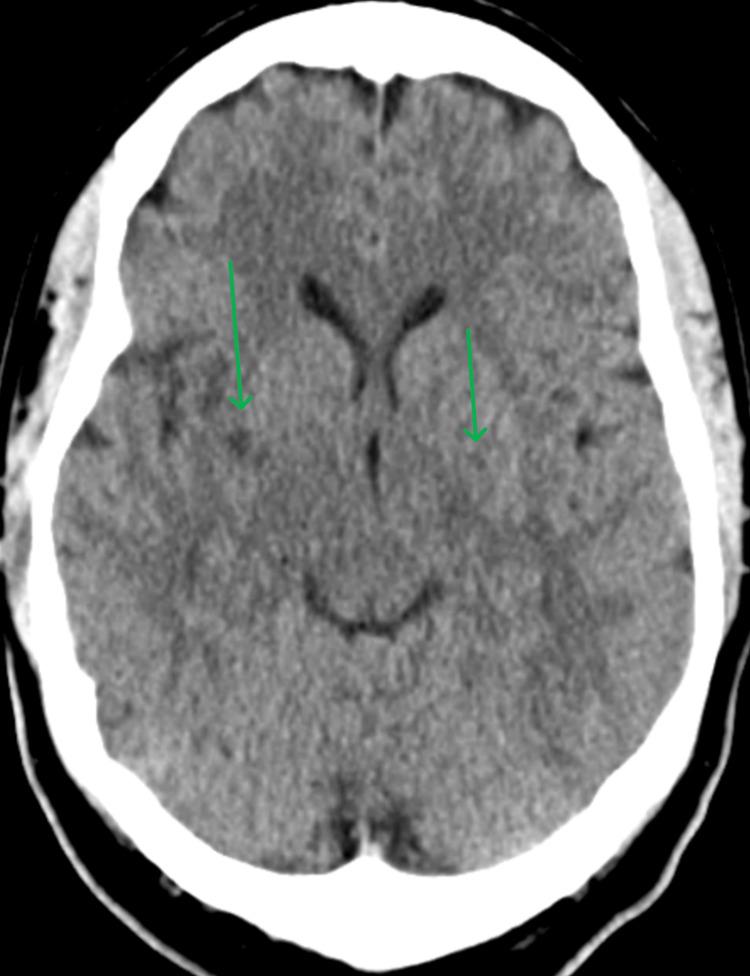

Tattoo-related infections are typically caused by gram-positive bacteria like and present with localized symptoms. However, this case describes a 48-year-old diabetic woman who developed bacteremia without any visible signs of infection at the tattoo site. She presented with systemic symptoms including fever, chills, and weakness, initially raising concerns for a neurological event. Laboratory tests confirmed gram-negative bacteremia, and the tattoo was identified as the likely source. The absence of local manifestations and the rare involvement of highlight the need for clinicians to consider systemic infections as a potential complication of tattooing, especially in high-risk patients. Early recognition and appropriate antibiotic therapy resulted in the patient's full recovery. This case underscores the importance of infection control during tattooing and vigilance for atypical presentations.